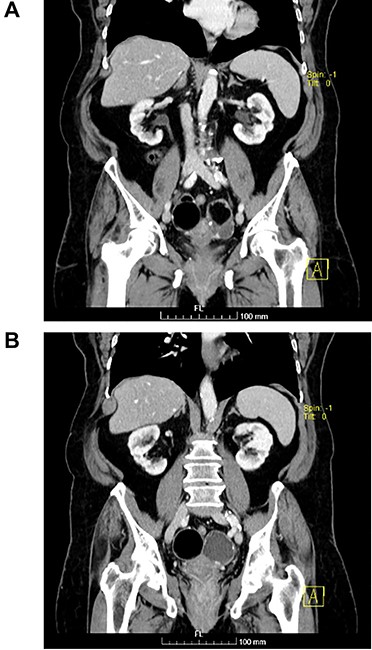

(A and B) Coronal images of MR showing bilateral ovarian teratoma.

The authors report the case of an asymptomatic 76-year-old female patient, referred to our Gynaecologic Clinic, due to suspicious adnexal lesions on a pelvic ultrasound (US). Menopause occurred at age 53. She had no history of abnormal uterine haemorrhage. Her menstrual cycles had been regular. She had had three gestations: two late abortions and one normal delivery, after which she breastfed. At our clinic, upon examination, vulva, vagina and cervix had no apparent lesions. The vaginal US revealed a right adnexal avascular cystic lesion of 65 mm, a left adnexal hyperechogenic cystic lesion of 60 mm, a normal sized uterus, a diffusely heterogeneous myometrium, an endometrial thickness of 8 mm and heterogenous intracavitary liquid. Her risk of ovarian malignancy assessment (ROMA) score was 28.1%, for a cut-off of 25.3%. Cancer antigen (CA) 125 and Human epididymis protein 4 (HE4) were 25.9 and 98.2, respectively. Lactate dehydrogenase (LDH), alpha fetoprotein (AFP) and beta human chorionic gonadotropin (bHCG) were normal. She subsequently had a magnetic resonance (MR) done (Fig. 1), which suggested bilateral ovarian teratoma. She also had an upper digestive endoscopy and a hysteroscopy that were normal and a computed tomography (CT) done (Figs 2–4) that showed: in the right adnexal region, a solid well-demarcated tumoural mass of 55 mm, with predominantly fat density, peripherical calcifications and a central hyperdense image (similar to a tooth), suggestive of a teratoma; in the left adnexal region, a predominantly cystic bilobated tumoural mass of 65 mm, with peripherical calcifications and an area of fat density, also suggestive of teratoma; and no additional disease. This case was presented at our Multidisciplinary Tumour Board, where surgery was proposed. Thus, she underwent exploratory laparotomy, peritoneal washing, total hysterectomy and bilateral adnexectomy, which ran uneventfully. Intra-operative frozen section excluded ovarian malignancy. She had an uneventful recovery and was discharged home on the third post-operative day. The pathological report revealed bilateral mature cystic teratoma with representation of the three germinative layers and thyroid parenchymal tissue (struma ovarii) (Fig. 5). Both ovaries were atrophic and had a cavitated lesion covered by respiratory epithelium with hyaline cartilaginous, adipose, smooth muscular and mucosa-associated lymphoid tissues (positivity for CD3 and CD20), seromucinous glands and thyroid follicles (homogenous positivity for thyroglobulin). Thyroid follicles were well differentiated, without features of malignancy. Fallopian tubes were normal. There were also uterine leiomyomas and a mucosal endocervical polyp. She was euthyroid and had a thyroid US done, which was normal. Follow-up at first post-operative month, remaining asymptomatic.